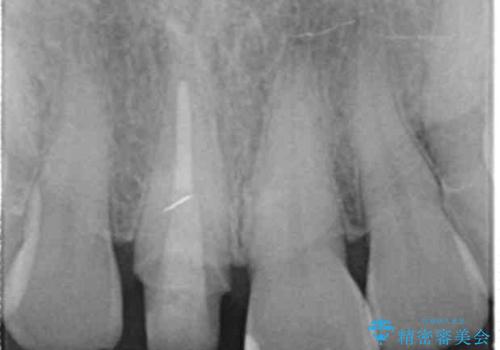

- 十数年前に治療した前歯のクラウンの歯ぐきの位置が変化し、黒いラインが見え審美性の改善を求めて来院されました。

ファイバーコアのやりかえを行ったのち、金属を用いないジルコニアクラウンによる再補綴を行い前歯の審美性の向上を計画します。